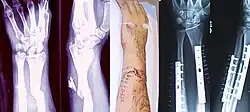

| Photo | Type | Description | Causes | Effects |

|---|---|---|---|---|

![]() |

Linear fracture | Parallel to the bone's long axis | ||

Transverse fracture | At a right angle to the bone's long axis | May occur when the bone is bent,[37]and snaps in the middle. | |

Oblique fracture | Diagonal to a bone's long axis (more than 30°) | ||

Spiral fracture or torsion fracture | At least one part of the bone has been twisted (image shows an arm-wrestler) | Torsion on the bone[37] | May rotate, and must be reduced to heal properly |

Compression fracture/wedge fracture | Usually occurs in the vertebrae, for example, when the front portion of a vertebra in the spine collapses due to osteoporosis (a medical condition which causes bones to become brittle and susceptible to fracture, with or without trauma) | ||

| Impacted fracture | Bone fragments are driven into each other | |||

| Avulsion fracture | A fragment of bone is separated from the main mass (image shows a Busch fracture) | |||

Comminuted fracture | The bone is shattered | often from crushing injuries[37] |